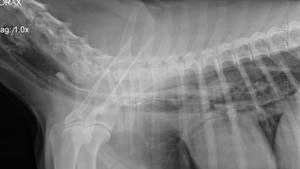

La miastenia a veces conlleva megaesófago

El megaesófago conduce a neumonía por aspiración

There may be an inciting febrile episode, but often no inciting cause is found. Animals present with weakness and exercise intolerance. There may be changes in bark, difficulty in swallowing and prehending food. Regurgitation and megaesophagus may be present.

Some cases present in a myasthenic crises where the animal has collapsed and is unable to rise. At this time, there may be muscle flaccidity. In uncomplicated myasthenia gravis (those without pulmonary pathology from aspiration pneumonia), the animal demonstrates progressive weakness on movement which improves with rest. Mild cases may be difficult to differentiate from animals with polymyositis.